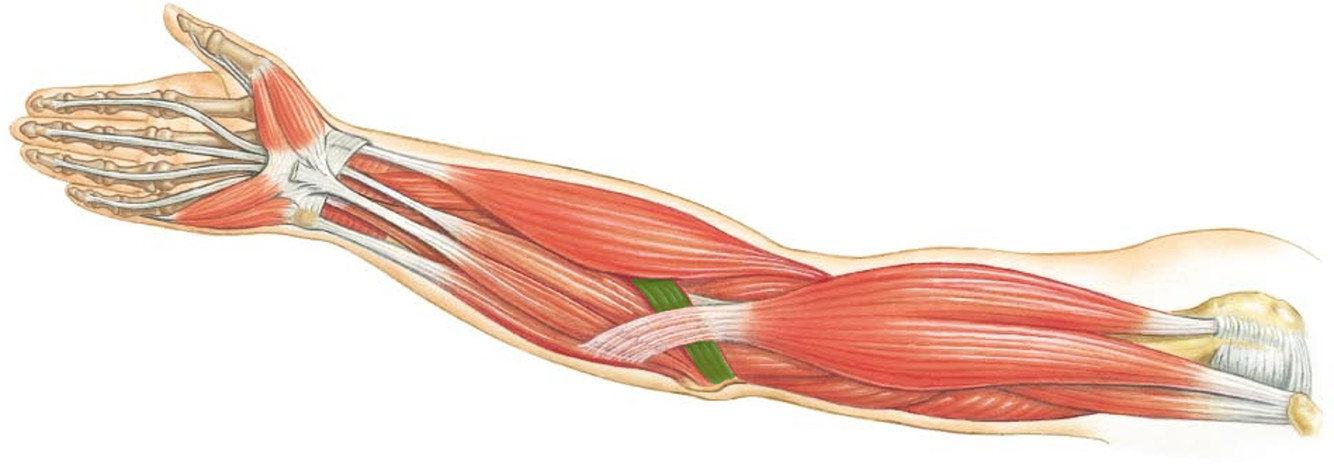

What is the innervation of this muscle?

Muscle - Flexor pollicus longus

Median nerve

C8 + T1

What is the innervation of this muscle?

Muscle - Pronator teres

Median nerve

Muscle - Flexor carpi radialis

Median nerve

Muscle - Palmaris longus

Median nerve

Muscle - Flexor digitorum superficialis

Median nerve

C7 - T1